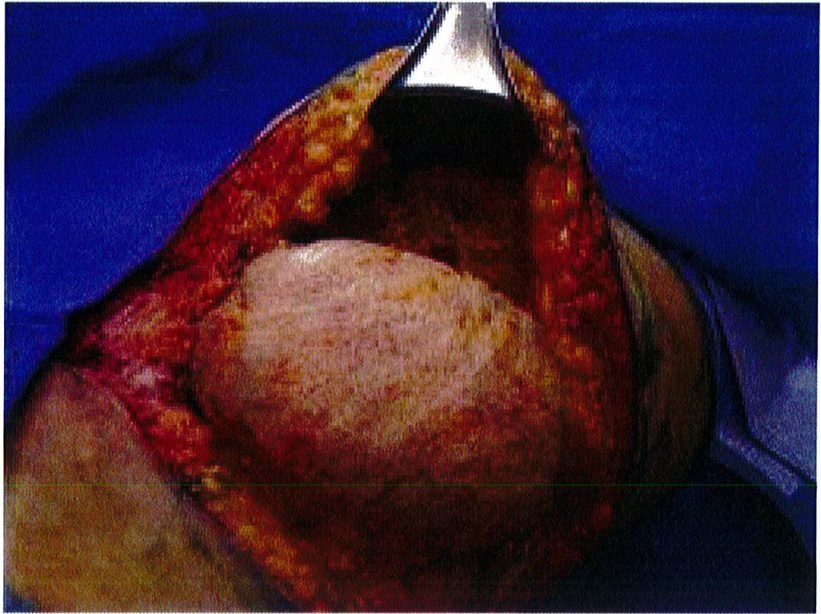

Hệ thống cân nông có thế được đánh dấu sau khi đã bộc lộ để xác định dễ dàng hơn, đồng thời các đường khâu cũng chính xác hơn. Sau đó dùng chỉ Mersilene số 1 khâu lớp cân nông lại với nhau và siết chặt chỉ để tạo thành một khối hình cầu (Hình 6). Kết quả thu được sẽ tương tự như khi bệnh nhân được đặt một khối implant cỡ lớn, với điểm hình chiếu tốt (Hình 7). Sau đó chúng được neo vào lớp cân nông phía trong (cạnh xương cùng) đã được bảo tôn trước đó. Lúc này có thể dùng chỉ Mersiline 3 (Hình 8). Cho tới nay không ghi nhận một trường hợp ứ máu hay tắc nghẽn ở tĩnh mạch vùng mô trung tâm nào.

ở hình 5) được khử biểu mô bằng dao tay hoặc dao điện để bộc lộ tới phần cân nông. Phần ranh giới của mô trung tâm này được bóc tách tới lớp cân cơ, làm chúng bị cô lập với các tổ chức xung quanh. Sau đó sử dụng mũi purse-string khâu đính phần cân nông lại với nhau rồi thít chặt chỉ để hình thành nên một đảo chứa các tổ chức dưới da, cân cơ (Hình 6), đồng thời bảo tồn được toàn bộ mạch máu thần kinh phía bên dưới. Chúng ta có thể thấy kỹ thuật này không phá hủy mô quá nhiều, đồng thời có thế sử dụng chính tổ chức dưới da đế tạo ra điểm hình chiếu thẩm mỹ cho mông. Mũi khâu dây rút cũng rất hữu hiệu ở đây vì chúng giúp co các mối chỉ cùng nhau, từ đó dồn và đẩy mô trung tâm lên thành một khối hình cầu, như đang sử dụng một khối implant vậy!

Hình. 7. Chỉ khâu được đảm bảo thắt chặt với khoảng 6 nút thắt. Sau khi thít chỉ thì trông mô trung tâm sẽ nhô ra nhiều hơn, là cơ sở để tạo ra điểm hình chiếu sau này.

Một túi bao bọc mô trung tâm được tạo ra dựa trên kích thước vùng vừa khâu purse-string. Túi này được đính ngang với lớp cân nông vùng mông (Hình 9). Chúng sẽ được kiểm tra thường xuyên để luôn ôm sát khối mô trung tâm.